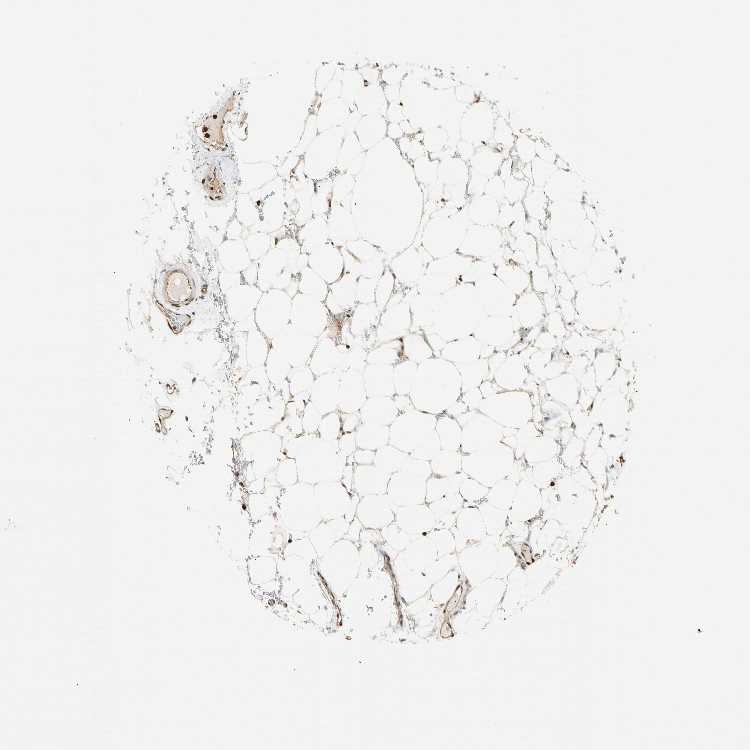

SOFT TISSUE 1 - Antibody stainingi

Antibody staining in the annotated cell types in the current human tissue is reported as not detected, low, medium, or high, based on conventional immunohistochemistry profiling in selected tissues. This score is based on the combination of the staining intensity and fraction of stained cells.

Each image is clickable and will lead to virtual microscopy that enables deeper exploration of all samples and also displays staining intensity scores, fraction scores and subcellular localization as well as patient and tissue information for each sample.

Antibody HPA007458

Fibroblasts Medium

Peripheral nerve Low